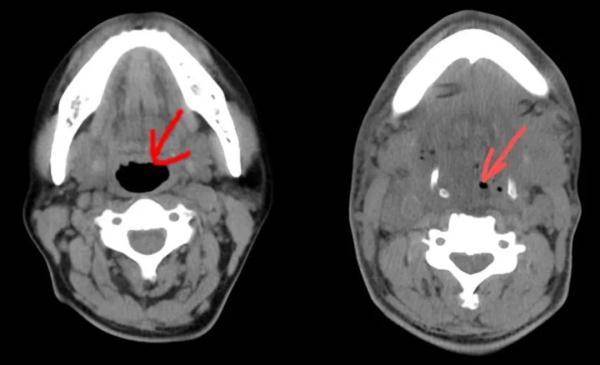

急診CT影像片子里,蔣先生的咽喉、口底、頜下等部位有大量積液和積氣,氣管已被擠得“消失”。

“兇險,患者是走了一趟鬼門關(guān)。”臺州恩澤醫(yī)療中心(集團)恩澤醫(yī)院口腔部主治醫(yī)師陳申國會診后說,這是典型的牙齒發(fā)炎導致的口底多間隙感染,這種病發(fā)展迅速,處理不當會有很高的致死率。現(xiàn)在患者雖然做了氣管切開,沒有窒息的危險,但還是需要盡快排膿引流,并且要阻止感染進一步擴散,以免給后續(xù)救治帶來更大麻煩。

蔣先生的病情一天天好轉(zhuǎn),術(shù)后第五天的CT影像片子里,終于出現(xiàn)了氣管的蹤跡,雖然只有黑豆那么大。能自主呼吸,意味著能拔氣切插管了。

左圖為正常氣管,右圖為患者術(shù)后第五天的氣管